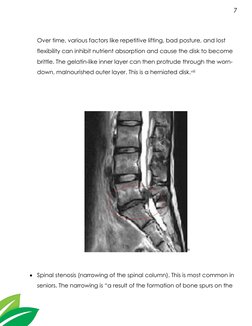

Over time, various factors like repetitive lifting, bad posture, and lost

flexibility can inhibit nutrient absorption and cause the disk to become

brittle. The gelatin-like inner layer can then protrude through the worn-

down, malnourished outer layer. This is a herniated disk.viii

ix